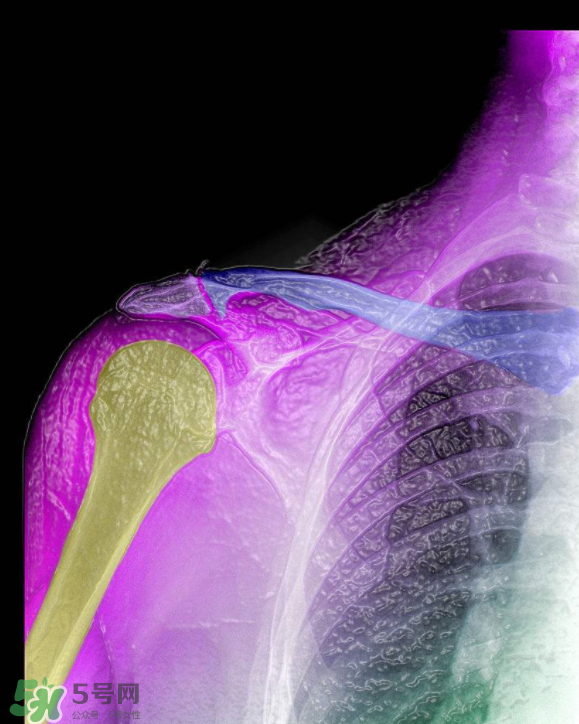

1、骨刺,多發(fā)于活動度最大、負(fù)重最多的頸椎、腰椎、骶椎、膝關(guān)節(jié)、足跟等部位。隨著年齡的增長,人的關(guān)節(jié)軟骨彈性會銳減,軟骨膠原纖維顯露,關(guān)節(jié)中部活動時極易磨損,其外周軟骨面便代謝性增殞肥厚,最后骨化形成骨刺。職業(yè)性持久用力、長期被迫體位不良、慢性或機(jī)械性刺激、跌打損傷等是誘發(fā)骨刺形成的原因。

2、骨刺患者一旦增生的骨刺刺激鄰近組織和壓迫神經(jīng)根時,就會出現(xiàn)局部或放射性骨刺的疼痛。主要表現(xiàn)為上肢麻痹、肩背疼痛、頸項(xiàng)僵硬、頭暈、胸悶不舒、心悸心慌、坐骨神經(jīng)痛、下肢麻痹痛、怕冷、膝關(guān)節(jié)腫痛、上下樓梯困難、不能下蹲等一系列骨刺的病理變化。如不及時治療,就會使骨刺的病情加重,增加治療難度。因此,這些都是骨刺形成的原因。